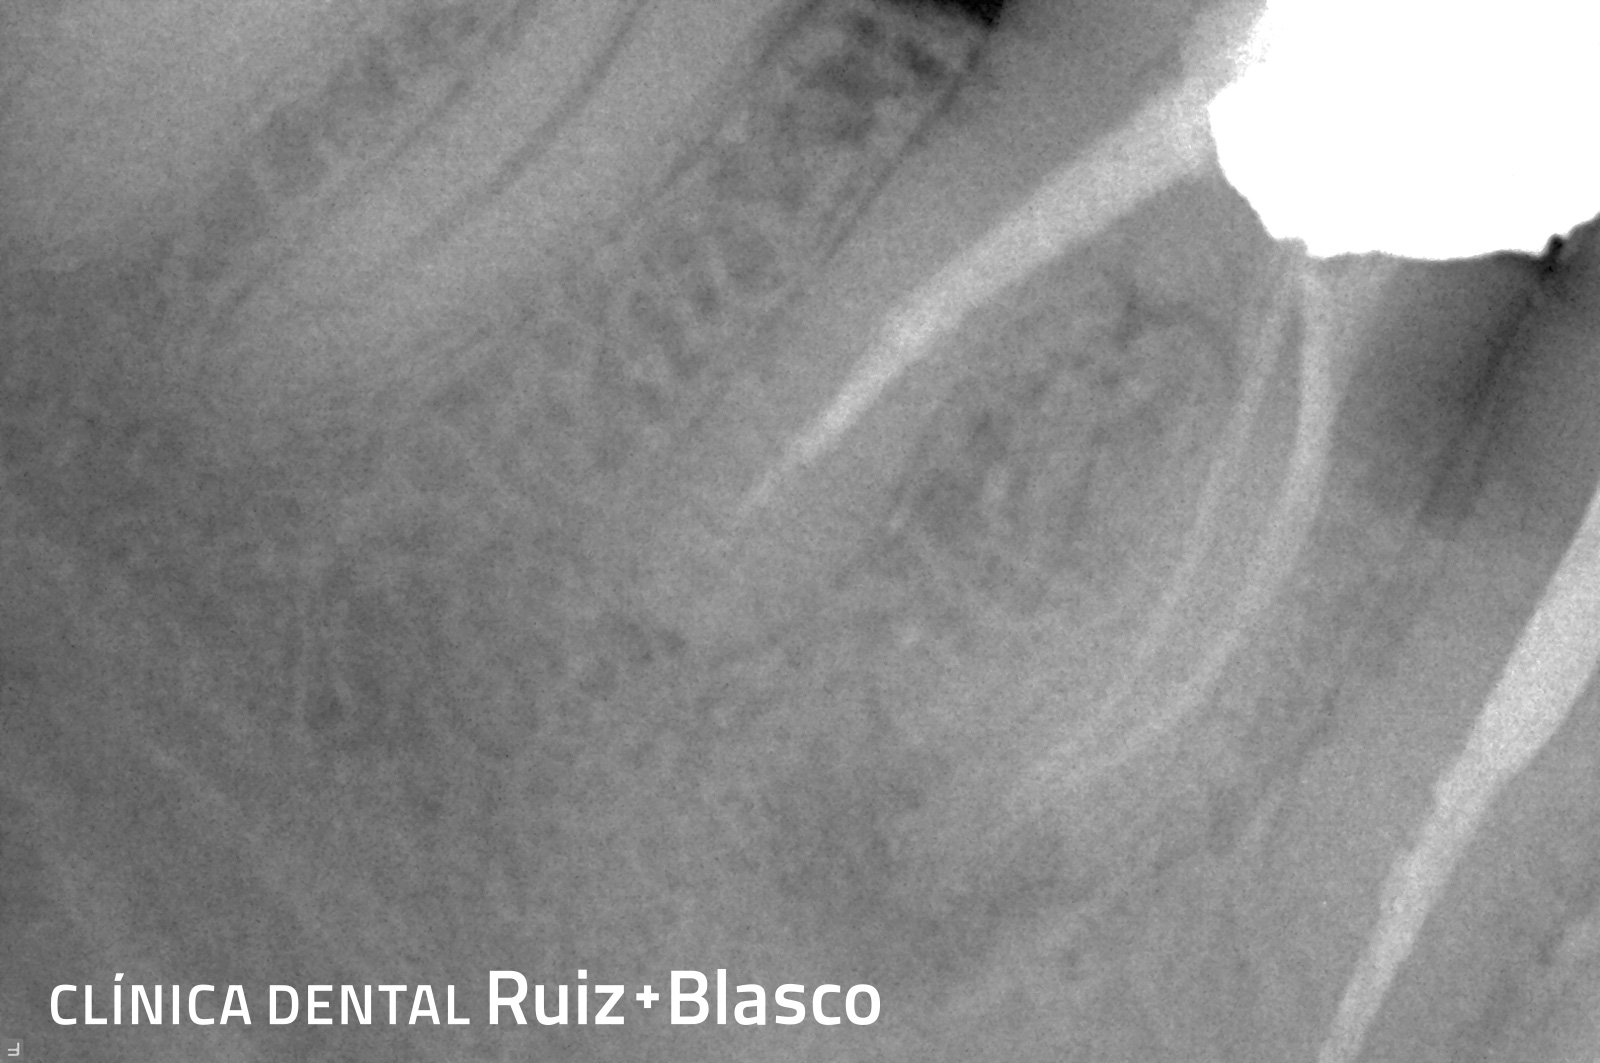

Caso 2

En este caso se puede contemplar el retratamiento de una endodoncia que no ha dado buen resultado y, por ello, había generado una lesión apical. Se puede observar cómo la lesión comienza a desaparecer después del retratamiento.